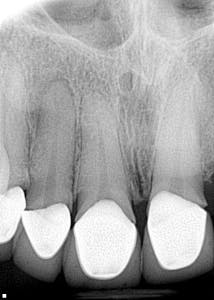

It’s one thing to see an overhang or open margin on one crown or filling, but when you see an entire mouthful of yuck, what do you tell the patient? I’m not a fan of throwing my colleagues in dentistry under the bus, but when I see questionable dental work, I believe the patient needs to know that there are concerns that affect two things: 1. the integrity of the tooth/teeth, and 2. the financial impact it could have.

So, when this patient presented to my office saying that all of her crown work was very recently done, I did a double take and asked, “Really?” Oy vey. Not fun. I recently posted this case in DE’s Breakthrough Clinical Facebook group. The responses are all enlightening and worth your read. With that being said, what would you say to this patient?